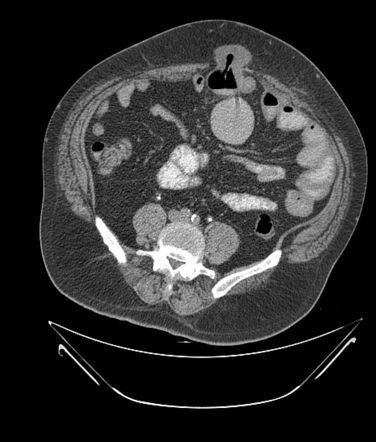

Richter hernia, also known as partial enterocele, refers to protrusion of only a small part of the entire circumference of the bowel. The hernia typically occurs in antimesenteric border. Congenital defects in the abdominal walls are usually associated with this type of hernia. Reference: https://pubmed.ncbi.nlm.nih.gov/16536253/#:~:text=Richter%20hernia%20(partial%20enterocele)%20is Image via: https://radiopaedia.org/articles/richter-hernia-1